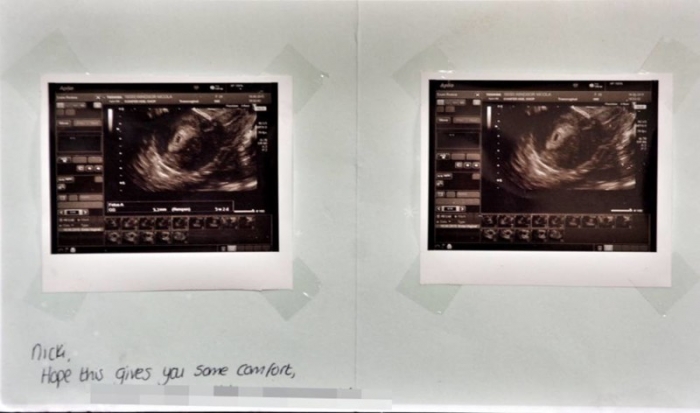

29-летняя мать-одиночка троих детей Ники Виндзор решила прервать свою четвёртую беременность. Для этого она обратилась в соответствующую клинику, где успешно провели операцию. Вскоре после этого женщина получила письмо из клиники, в котором показывались снимки УЗИ её нерождённого ребёнка.

Сначала Ники восприняла это, как красивый жест со стороны врачей. Но рассмотрев эти фотографии, у неё начало существенно ухудшаться психическое состояние. «Я чувствую себя опустошенной. Мне до сих пор снятся кошмарные сны, где я вижу снимки своего мертвого плода», — говорит она.